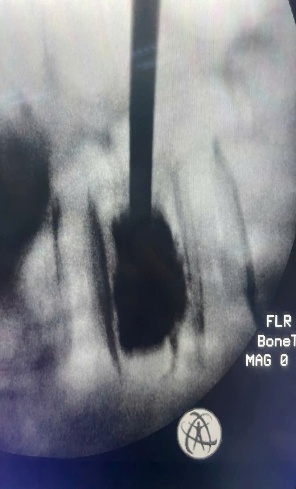

Bơm ciment sinh học điều trị xẹp đốt sống do loãng xương, trên màn hình tăng sáng ( máy C-Arm)